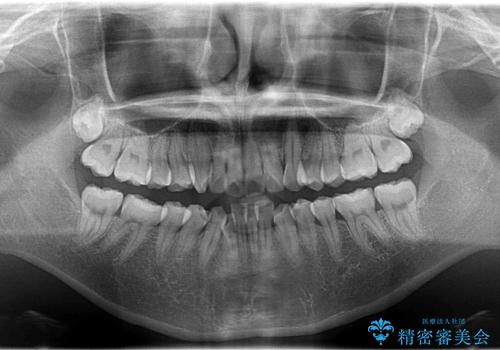

- 前歯が出ていることと、下の歯のがたがたで歯磨きがしにくいことを主訴に来院されました。

マウスピース矯正の希望があり、ワイヤーリカバリの可能性を伝えたうえでインビザライン抜歯矯正を行っています。

来院が途中途絶えたこともあり、4年ぐらい期間がかかりましたが、インビザラインだけで治療を終えることができました。